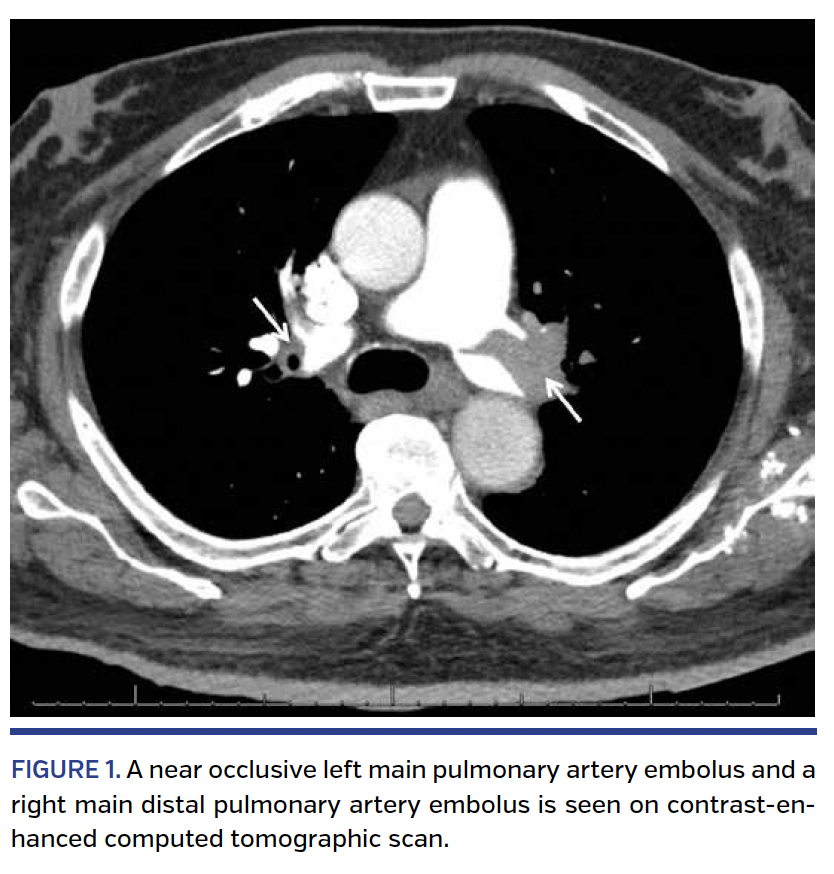

A 76-year-old male presented with a submassive pulmonary embolism (PE) despite having an inferior vena cava (IVC) filter. Contrast-enhanced computed tomographic scan revealed left and right main pulmonary artery emboli (Figure 1). Transthoracic echocardiography revealed moderate right ventricular dysfunction and dilation, and N-terminal proBNP was 3970 pg/mL (reference range, <450 pg/mL). An acute deep vein thrombosis in the left common femoral vein was found by venous duplex ultrasound (Figure 2). Venography showed the IVC filter with struts extending into both the left and right renal veins (Figure 3). Because of the mobile nature of the thrombus and potential for embolization, a new infrarenal IVC filter was deployed below the level of the prior filter. Pulmonary angiography confirmed the finding of bilateral pulmonary emboli (Figure 4). EkoSonic Endovascular System (EKOS Corporation) catheter-directed, low-dose fibrinolysis (total dose, 24 mg) was initiated via bilateral catheters (Figure 5) along with intravenous heparin. Repeat pulmonary angiogram the following day revealed significant improvement of the filling defects bilaterally (Figure 6). The patient was asymptomatic after 12 hours of therapy, and was discharged from the hospital on warfarin.